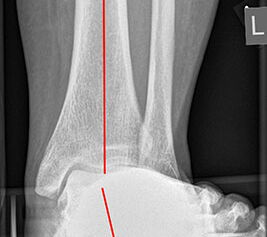

Abbildung 4

Lagerung des Patienten in Seitenlage, das zu operierende Bein oben z.B. mit einem Tunnelkissen (Abbildung 4). Weiche Lagerung des unten liegenden Beins zur Prophylaxe von Druckschäden am N. peronaeus in Höhe des Fibulaköpfchens.